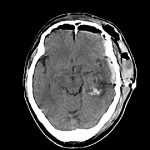

’12_156

'12年9月

50代

脳腫瘍

断層撮影

手術前1

No.’12_156 手術前1